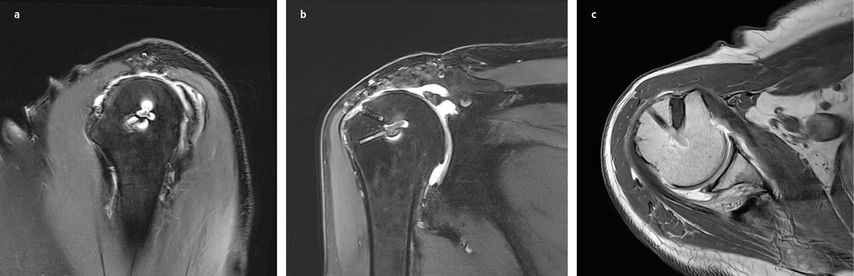

Magnetresonanztomografie (MRT): Das MRT, häufig auch als hochauflösende MRT-Arthrografie, spielt eine zentrale Rolle in der Diagnostik. Nach operativen Eingriffen kann die Aussagekraft jedoch durch Metallartefakte oder Narbengewebe eingeschränkt sein, was die Interpretation erschweren kann. Bei der Interpretation des MRTs muss berücksichtigt werden, dass sich die Rotatorenmanschette auch nach bis zu 12 Monaten noch in der Heilungsphase befinden kann. Areale mit Signalanstieg können einer Reruptur ähneln. Rerupturen sind am deutlichsten in den T2- und PD-gewichteten Schichten beurteilbar.25

Der Muskelstatus ist entscheidend für den Erfolg der Revisionschirurgie und wird durch die Goutallier-Klassifikation hinsichtlich der fettigen Infiltration beurteilt. Eine geringe Infiltration (Grad 0–1) ist vielversprechend für eine erfolgreiche Rekonstruktion, während eine höhere Infiltration (Grad 2–4) das Risiko für eine (Re)Reruptur und progrediente Muskeldegeneration erhöht. Goutallier et al. zeigten mit einer klinischen Folgestudie nach Index- Beschreibung der Klassifikation im CT 1994, dass präoperative Atrophien mit höheren Rerupturraten assoziiert sind, insbesondere im fortgeschrittenen Stadium. Besonders die fettige Infiltration wurde als wichtiger negativer Prognosefaktor identifiziert.38

In der Gruppe der Rerupturen konnte außerdem eine Progression der strukturellen Veränderungen – auch im angelagerten Muskel (ISP bei SSP-Reruptur) – gezeigt werden. Diese fettige Degeneration korreliert dabei signifikant mit dem klinischen Outcome.39 Die Klassifikation von Rotatorenmanschetten-Rerupturen erfolgt typischerweise nach Sugaya und unterscheidet fünf Typen (Tab. 1).40

Abb. 3: Arthroskopische Revisionsoperation nach erneuter arthroskopischer Ankerplatzierung